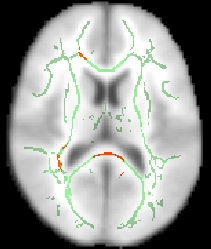

The script finishes by telling you to check whether a suitable threshold for the mean FA skeleton is 0.2 (a typical value used by the next script). For example, load the 4D FA data and the skeleton into FSLView:

cd stats

fsleyes all_FA -dr 0 0.8 mean_FA_skeleton -dr 0.2 0.8 -cm green

The -dr option sets sensible display range options, and in the case of the skeleton image, also controls the thresholding applied. Now turn on the movie loop; you will see the mean FA skeleton on top of each different subject's aligned FA image. If all the processing so far has worked ok the skeleton should look like the examples shown here (see the TBSS paper for more examples of different subjects' results underneath the skeleton). If the registration has worked well you should see that in general each subject's major tracts are reasonably well aligned to the relevant parts of the skeleton. If you set the skeleton threshold (in FSLeyes, the lower of the display range settings) much lower than 0.2, it will extend away towards extremes where there is too much cross-subject variability and where the nonlinear registration has not been able to attain good alignments. Remember the skeleton threshold for the next stage.

All of the above (apart from setting the skeleton transparency, which has to be done by hand in the GUI) can be carried out with a single command (see first example image):

fsleyes $FSLDIR/data/standard/MNI152_T1_1mm mean_FA_skeleton -cm green -dr 0.2 0.7 tbss_tfce_corrp_tstat1 -cm red-yellow -dr 0.95 1